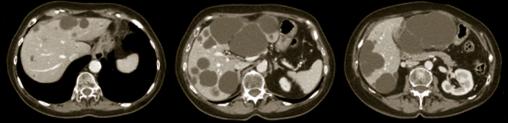

Polykystose hépatique

2. Polykystose hépatique